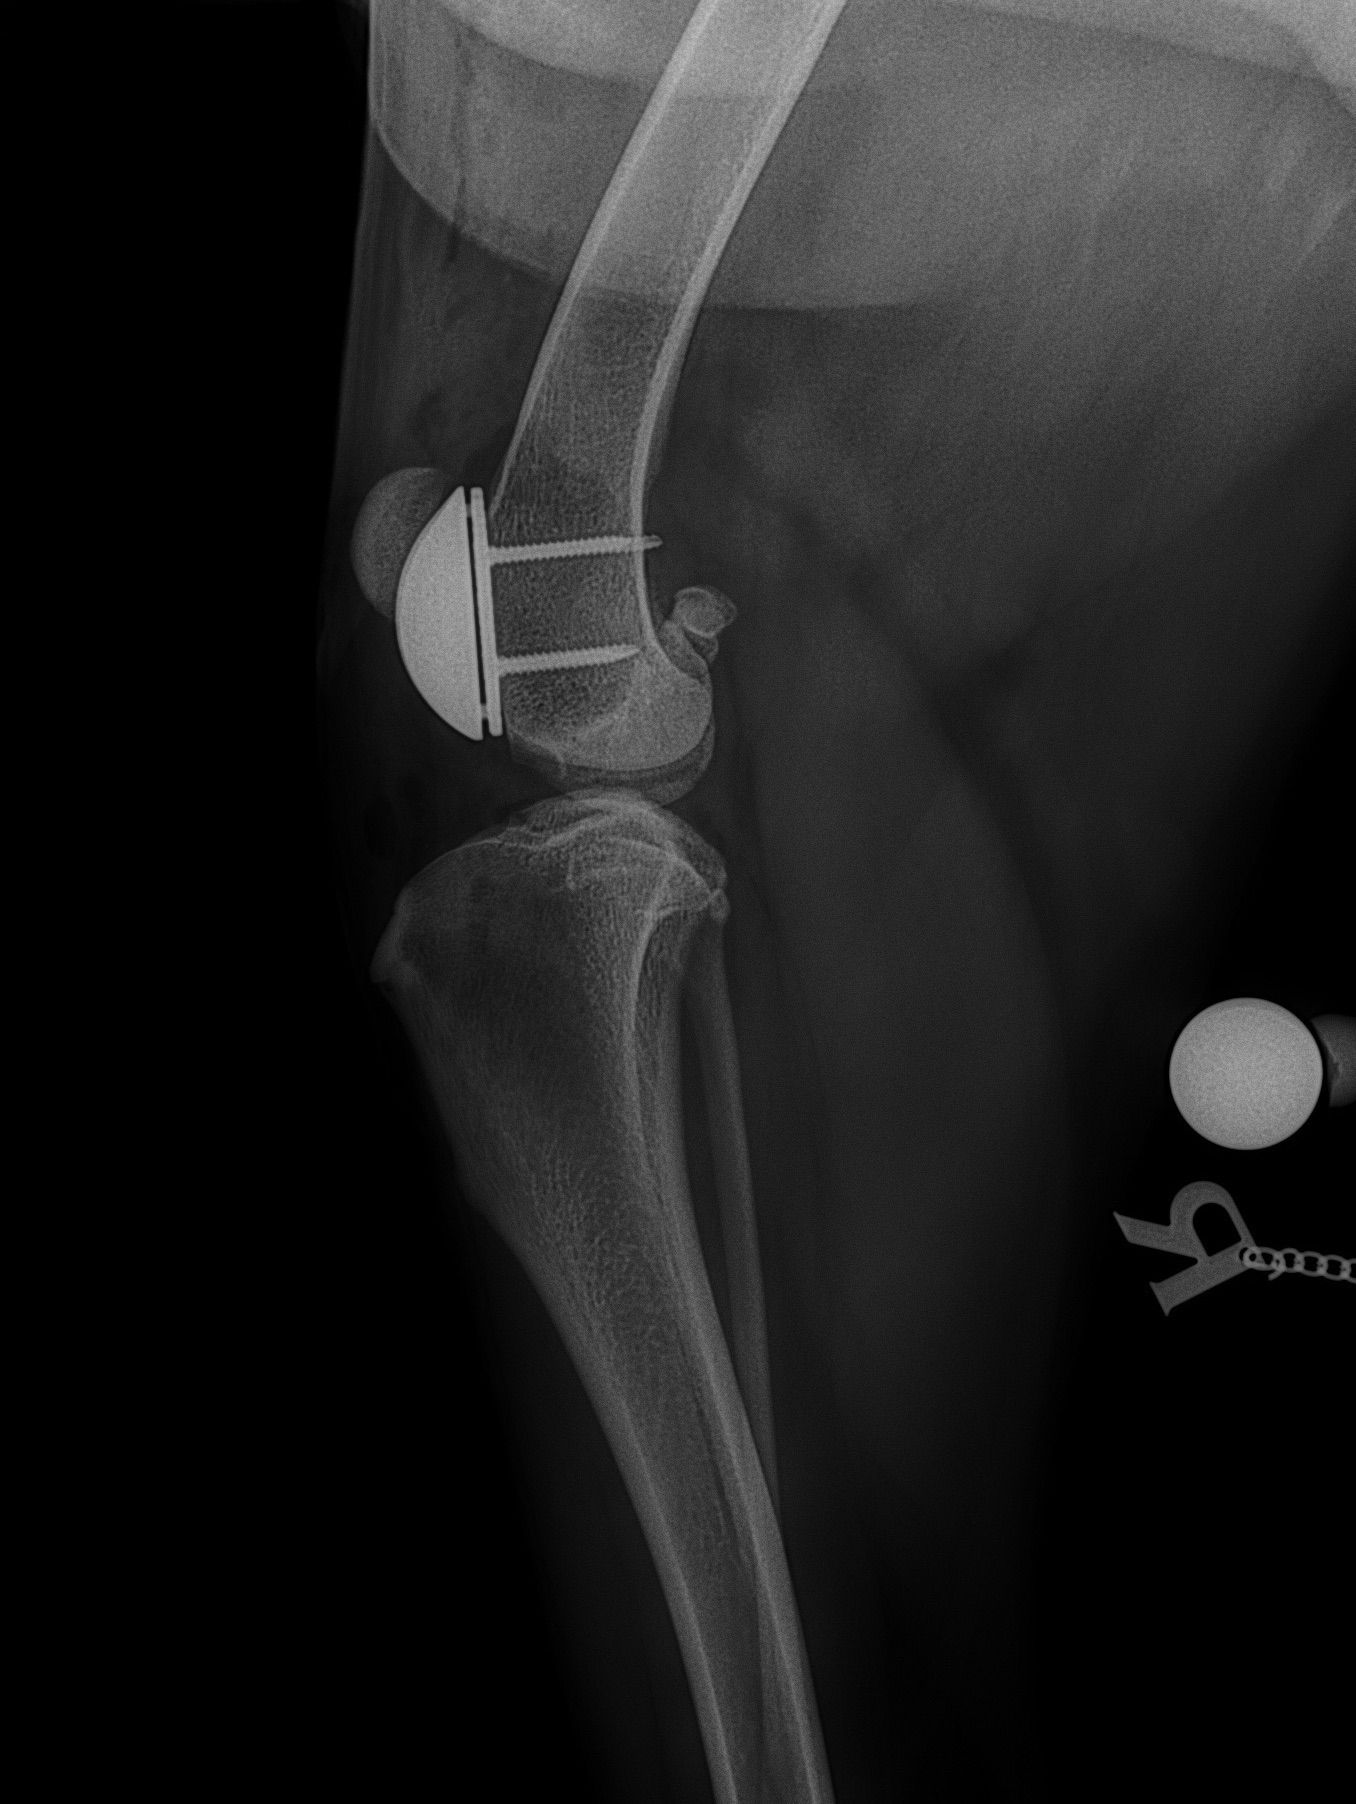

Specialisatie Patella luxatie ( losse knie)  kruisband herstel bij hond en correctieve osteotomies , kunstgroeve, kunstknie bij hond en kat .

April 2009 TTA for treatment of cruciare deficient stifle in dogs  Zwitserland

Mei 2014   AOVET AO master class advanced corrective osteotomies: Rear limb and patella luxatie

April 2019  KYON Corrective osteoyomy of the hind limb and patella groove  Zwitserland

PGR patella groeve raplacement.